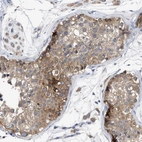

Immunohistochemical staining of human cerebral cortex shows strong cytoplasmic positivity in neuropil and neurons.